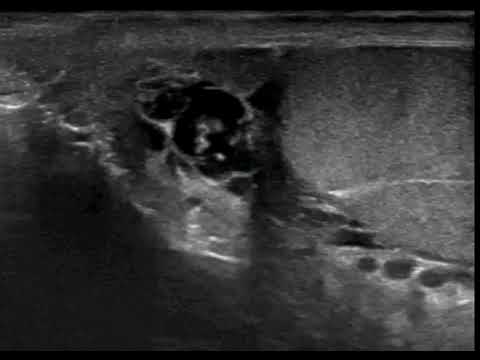

Врачи индийской больницы засняли на видео "танец" паразитов внутри мошонки пациента